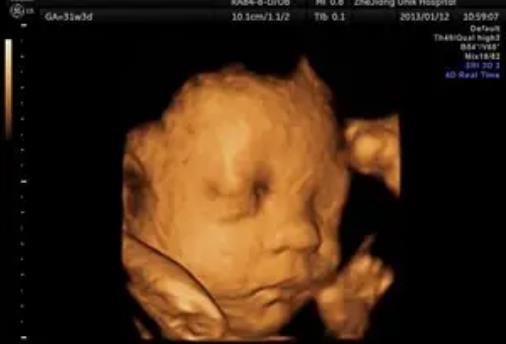

雖然懷孕的時(shí)候醫(yī)生是絕對(duì)不會(huì)告訴家長(zhǎng)胎兒性別的,但大多數(shù)家長(zhǎng)還是按捺不住好奇心,總想自己從各種檢查單子上看出男女差異。網(wǎng)上一直流傳懷女孩的標(biāo)志是圓形的孕囊,要是B超單有這個(gè)一般是女孩,那么現(xiàn)實(shí)真是這樣嗎?除了孕囊還有別的懷女孩標(biāo)志嗎?下面小編就帶大家來(lái)了解一下。

1、圓形的孕囊:B超單上可以看到孕囊,要是孕囊是長(zhǎng)形的,那么就是男孩,要是孕囊呈圓形或橢圓,那可能就是女孩。

2、較高的胎心率:女寶寶的胎心率一般在150以上,而男寶寶的胎心率一般在140左右。

3、背朝外的胎位:這是由很多孕媽發(fā)現(xiàn)的規(guī)律,女孩子喜歡背朝外,面朝里,姿勢(shì)很像在和媽媽擁抱一樣。

4、雙頂徑和股骨的差小于2:雙頂徑是胎兒頭部的橫向長(zhǎng),而股骨則是胎兒大腿骨的長(zhǎng)度,由于男女體型差異,女孩子的頭和腿的差異很小,一般都會(huì)小于2。

以上就是網(wǎng)上流傳的生女孩的標(biāo)志,但只要生過(guò)孩子的人都知道,這其實(shí)一點(diǎn)科學(xué)依據(jù)都沒(méi)有,只是為了滿足寶爸寶媽的好奇心而已,大家看看就行,不要當(dāng)真,最重要的還是胎兒的健康發(fā)育。